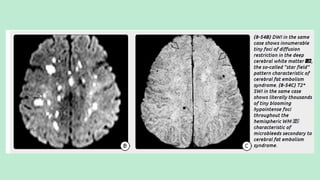

CEREBRAL FAT EMBOLI (FES)

Hallmarks is:

Arteriolar fat emboli with perivascular

microhemorrhages.

Imaging findings reflect the effects of the fat

emboli (i.e., multifocal tiny strokes and

microhemorrhages) on brain tissue, not the

fat itself.

NECT scan: Generally normal

MRI: MR shows numerous (average = 50) punctate or confluent

hyperintensities in the cerebellum, basal ganglia, periventricularWM, and GM-

WM junctions on T2/FLAIR.

DWI shows innumerable tiny punctate foci of diffusion restriction in multiple

vascular distributions, the "star field“ pattern.

The deep watershed border zones are commonly involved.

Solitary or multiple small hypointense "blooming" foci can be identified in up

to one-third of all FES cases onT2* GRE. SWI discloses innumerable (>200)

tiny "black dots" in the majority of patients.